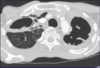

Q

What is this?

A

Sporotrichosis